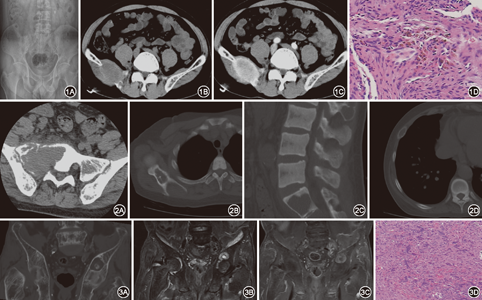

本组15例共34处病灶,多骨受累者11例,单骨受累者4例;累及髂骨多见,共7处,肋骨、股骨、椎体及附件各5处,颅骨3处,肩胛骨、胫骨、耻骨各2处,锁骨、胸骨、髌骨各1处。骨质破坏32处,其中膨胀性破坏26处,溶骨性骨质破坏6处。X线表现:全身弥漫骨质疏松13例,全身弥漫骨质硬化2例,表现为多发膨胀性骨质破坏,部分病灶为溶骨性骨质破坏,其内可见片状、条索状钙化/骨化影,病灶边缘可见硬化边。CT平扫呈等或稍低密度,其中内部可见点、条状骨化影23处,邻近骨皮质反应性增生硬化12处,病灶存在软组织肿块13处,2例行增强扫描均为明显强化。发生在颅骨者3处,其中1处为局限性溶骨性骨质破坏,另2处表现为弥漫骨质密度增高,内、外板边缘模糊。MRI表现:T1WI呈不均匀低信号,T2WI呈不均匀高信号。2例增强扫描示1例明显不均匀强化,1例轻中度强化(图1,图2,图3)。

15例均有甲状旁腺病变,其中增生9例,腺瘤6例。骨穿刺或切除术后病理共同特点:破骨细胞呈片状分布,间质内大量梭形成纤维细胞,组织细胞胞体及间隙内散在含铁血黄素沉积,不等量的细条状骨小梁,其周边有骨母细胞围绕,部分病灶可见大量红细胞,少量中性粒细胞。

甲旁亢所致骨改变,早期表现主要为骨质疏松及骨膜下骨吸收[9]。结合文献报道及本组病例分析,棕色瘤典型影像学表现为囊性膨胀性骨质破坏,骨质破坏区可伴有软组织肿块,强化形式多样。病理学上骨质破坏早期骨小梁间充满大量的纤维组织,富含血管,后期有较多的胶原纤维增生[5],早期强化明显,中晚期强化减低。本组4例增强扫描患者中,明显强化3例。棕色瘤的骨质破坏边缘多伴骨质增生硬化,临近骨皮质增厚[10],多发生在病变晚期,椎体边缘由于重叠效应很难观察到[11],肋骨病变中多有此征象,该征象对于棕色瘤同恶性骨肿瘤的鉴别具有重要的意义,可能与棕色瘤病灶周围有成骨细胞,形成新的骨质有关。本组有12处病灶存在该征象,与文献报道相符。文献中很少提及棕色瘤病灶内存在骨化/钙化影,本组中有23处病灶中存在该征象,可能的病理基础为纤维组织中有新形成的骨样组织及成熟和不成熟的骨小梁,骨小梁周围有成排的骨母细胞及较多的破骨细胞吸收现象[12]。骨皮质常有变薄,部分可有缺失,无骨膜增生,可出现病理骨折及骨骼畸形也是棕色瘤常见影像学表现。发生在颅骨表现为弥漫骨质密度增高,内、外板边缘模糊[6]。